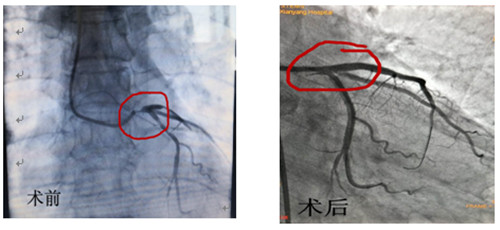

術(shù)前術(shù)后造影對(duì)比

12月16日早上8點(diǎn)30分手術(shù)如期進(jìn)行,術(shù)前IVUS評(píng)估:左主干自口部至末端彌漫狹窄,最小管腔面積<1mm2,斑塊負(fù)荷程度>90%,主要為纖維脂質(zhì)斑塊,無明顯鈣化,回旋支開口尚可,前降支近段主要為纖維脂質(zhì)斑塊,亦無明顯鈣化。據(jù)此,手術(shù)方案定為:前降支近段至左主干口部串聯(lián)植入2枚支架,回旋支近段1枚支架,無需旋磨、切割,支架植入后IVUS評(píng)估:支架膨脹、貼壁良好,左主干口部支架梁覆蓋完全,手術(shù)完美收官。此系心內(nèi)二病區(qū)左梅主任及其團(tuán)隊(duì)在導(dǎo)管室配合下完成的我院首例自主IVUS指導(dǎo)下左主干PCI。